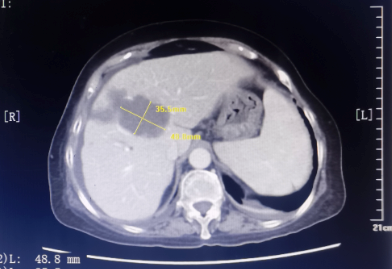

患者为67岁女性,1年余前诊断胃腺癌晚期,肝脏、骨骼及淋巴结多发转移,本次入院复查发现肝脏病灶进展,科主任白俊主任医师、主管医生刘莹主治医师详细分析并与患者家属沟通病情,考虑患者既往接受多线系统性抗肿瘤药物治疗,且治疗过程中多次出现剂量限制性骨髓毒性,继续更换药物治疗的选择空间不多,推荐超声引导下微波消融部分肝脏转移病灶,以期为后续继续免疫及靶向治疗创造在体瘤苗的机会。段宝军副主任医师认真阅片后,考虑该例患者肝转移病灶大(最大径超过5厘米),且毗邻膈肌、肝左静脉及第一肝门等重要结构,因此采用3D可视化手术规划系统设计微波消融方案,在麻醉科常建华副主任医师及手术室的精心配合下,顺利完成了肝转移病灶微波消融手术。

超声引导下肝癌病灶微波消融术微创、经济,且无辐射,是指南推荐的肝癌标准治疗方案。但由于重复进针的人为误差、热传导不足、肝脏储备功能等因素的影响,大肝癌的消融治疗难以做到根治性消融,尤其是危险区域的肝癌病灶微波消融易发生严重并发症,导致超声引导下微波消融的治疗作用与外科手术存在一定差距。

3D可视化系统可通过分析、融合、渲染等处理患者术前增强MRI或CT影像数据,在系统上创建不同的模块(如正常肝、病肝、门静脉、肝静脉等模块),对肝内外胆管及动、静脉系统重建,分析病灶与周围重要器官的关系,以及可能损伤的结构,确定安全边界,模拟进针路径、针数、消融时间,计算肿瘤体积、剩余肝体积,用不同颜色代表进针次序,对较大肿瘤需不断调整针的空间位置使热场范围能够覆盖安全边界。该技术辅助超声引导下肝癌微波消融术可提高消融成功概率、有利于制定更加合理的手术方案,减少消融手术并发症的发生,为肝癌的精准、安全消融治疗提供了新的选择。